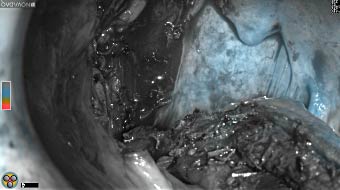

Skull Removed

Brain Exposed

Tumor Visible

Tumor Removed

White light

Fluorescence (heat map)

Fluorescence (black and white)

As the tumor was located beneath the brain surface (as indicated in presurgical MRI), minimal fluorescence was detected through the intact dura. The tumor lied beneath the area (dashed line: expected incision path) where faint fluorescence signal showed up on the brain surface. A clear fluorescence signal was visible in the tumor when the surgeon reached the tumor (dashed circle). Very little fluorescence remained in the wound bed after surgical removal of the tumor. You may also want to read the 2019 interview with Dr. Li and Dr. Rosenthal on novel imaging technologies to identify brain cancer.